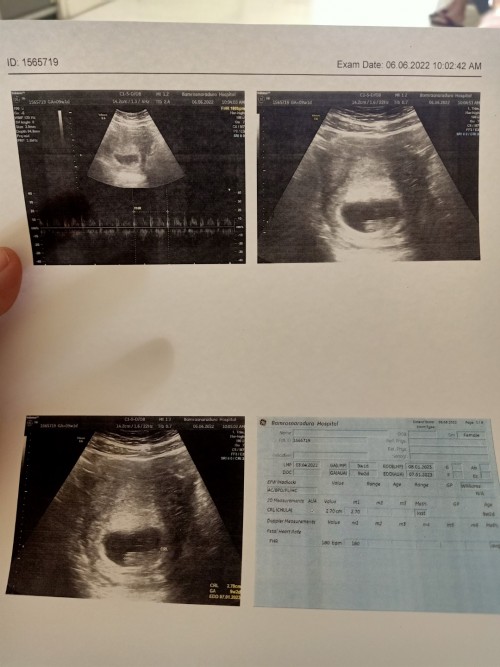

ตั้งครรภ์ 10 วีค

ประมาณ 3 เซนค่ะ 10 วีค

ท้องแรกค่ะ 9w 2.35 cm. ค่ะ

3เซนจ้า มาเป็นคู่😆

เข้า10 w เเล้วค่ะ👼❤️

12 3ค่ะ ซาวครั้งแรก7 5